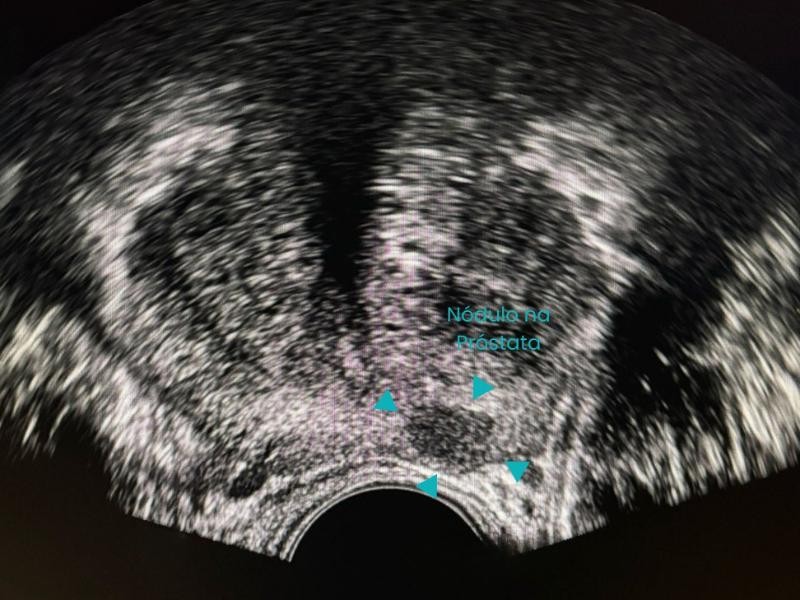

Conquistou o primeiro lugar no exame nacional da SOBRICE e se destaca em procedimentos minimamente invasivos, como ablação de tumores e biópsias guiadas. Atende nos melhores hospitais de São Paulo, incluindo o Hospital Nove de Julho e Vila Nova Star.